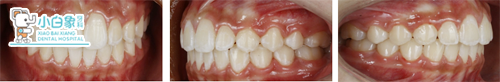

患者:***    女     13岁

主诉:牙不齐,求治。

现病史:患者换牙后发现牙列不齐,影响美观,来诊。

双颌稍前突 治疗前

治疗前

安氏一类错合

深覆合 深覆盖二度

牙列拥挤